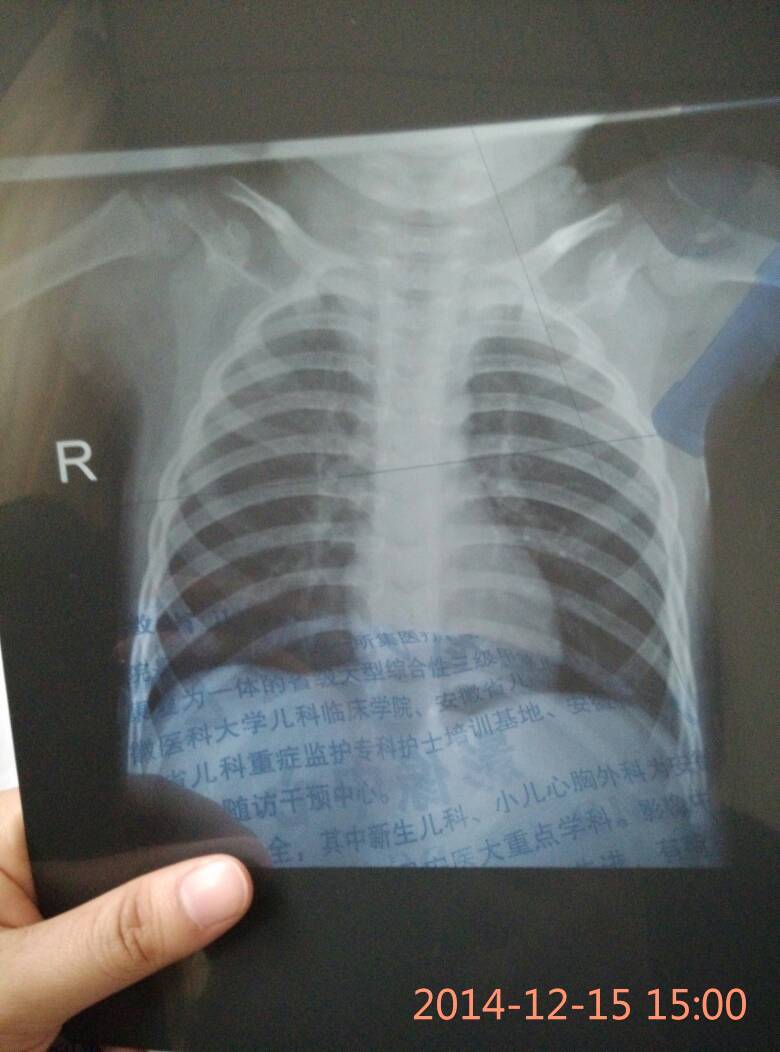

宝宝拍的X光胸片出来了,正常吗? 点击展开 匿名用户 2014-12-15 15:13 为您推荐: 其他回答 你好,宝宝可能有点支气管炎,请结合临床,其他没有太大的问题。 yizhujunve 2014-12-15 19:53 相关问题 怀孕可以拍X光吗?拍胸片的那种 备孕期间办健康证拍了x光胸片,网上查了说要等三个月才能要小孩,是真的吗?去医院问了医生也这么说,但是我感觉站上去到拍完才五六秒的呀! 孕初期(着床)拍x光胸片后 4月12号未次月经,5月3号两个人一起,5月12号体检拍了胸片